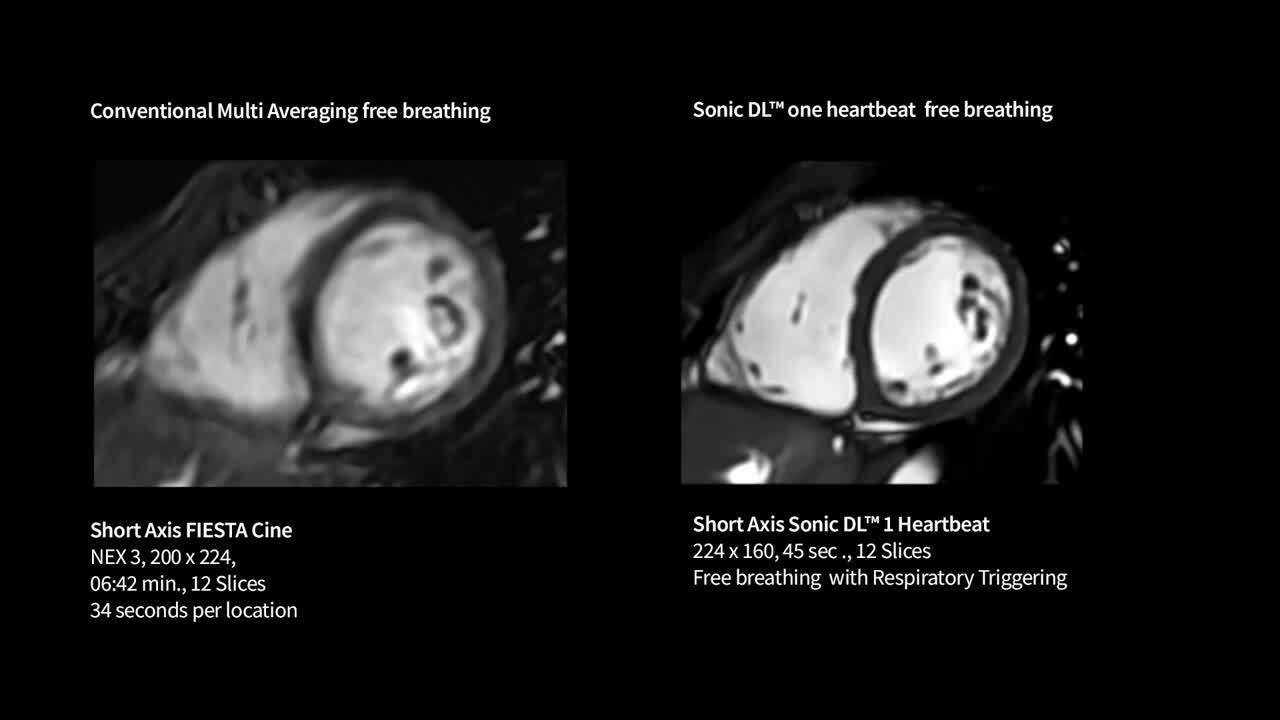

Life-Speed imaging

Achieve up to 12X acceleration and up to 83% scan time reduction*